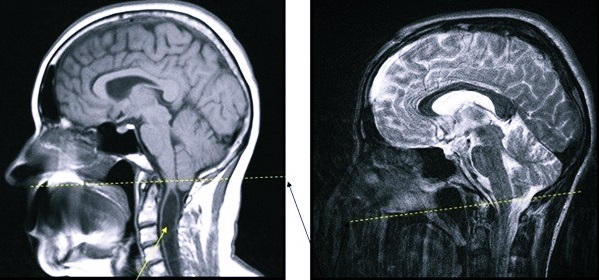

Врачи отмечают, что аномалия Арнольда-Киари представляет собой серьезное неврологическое заболевание, которое требует внимательного подхода к диагностике и лечению. Специалисты подчеркивают, что симптомы могут варьироваться от головной боли и головокружения до более серьезных неврологических нарушений. Важно, чтобы пациенты, у которых есть подозрение на данное заболевание, проходили полное обследование, включая МРТ, для точной диагностики.

В связи с этим в последнее время наиболее часто применяется МРТ (магнитно-резонансная томография) – единственный простой и достоверный способ диагностики данной аномалии развития головного и спинного мозга. Поскольку для ее проведения необходима полная обездвиженность человека, то для обследования маленьких детей вводят в состояние так называемого медикаментозного сна.

Помимо МРТ головного мозга, неврологи могут дать направление на проведение МРТ грудного и шейного отделов позвоночника. Показанием для этого является подозрение на параллельное развитие сирингомиелических кист либо менингоцеле. Еще одним важным преимуществом данной методики является то, что она помогает обнаружить даже слабо выраженные нарушения в развитии центральной и периферической нервной системы, которые могут сопровождать аномалию Киари.